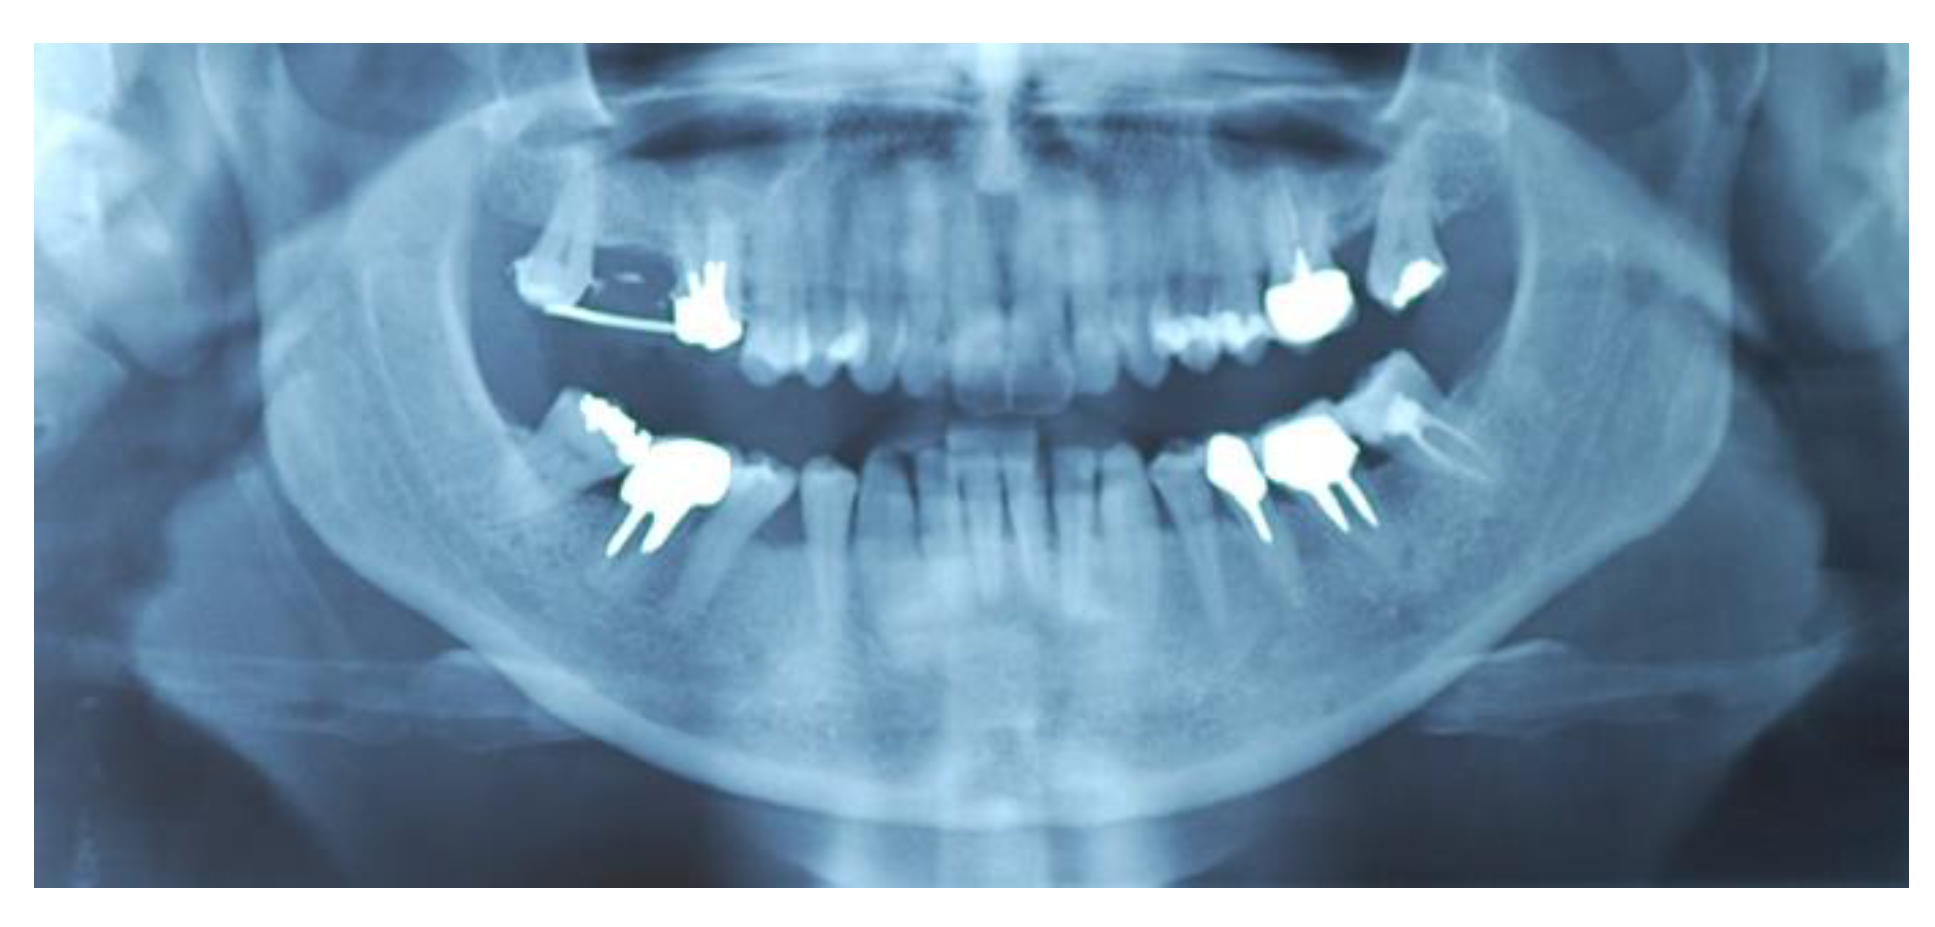

2. Materials and Methods

2.1. Surgical Procedures